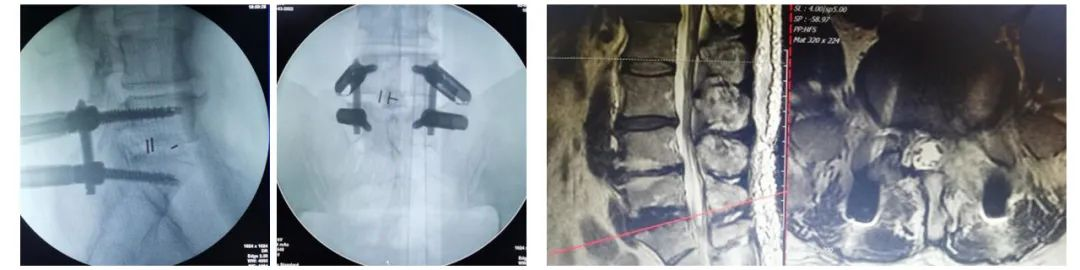

术后X线透视图及术后CT、Mr复查:内固定及植骨在位良好;椎间盘完全摘除,神经根松弛